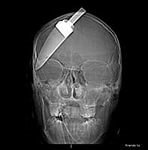

2 января в больницу города Череповца из подъезда дома № 26 на Шекснинском проспекте доставлен 18-летний череповчанин, который жаловался на сильную головную боль. Юноша рассказал, что совсем недавно разнимал дерущихся друзей и обо что-то сильно ударился. Результаты обследования череповчанина показали, что у пациента в полости черепа находится металлический осколок ножа. Молодой человек находится в тяжелом состоянии под постоянным наблюдением врачей. В настоящий момент обстоятельства произошедшего устанавливаются сотрудниками уголовного розыска. По собранным материалам будет принято процессуальное решение, сообщает пресс-служба УМВД России по Вологодской области.